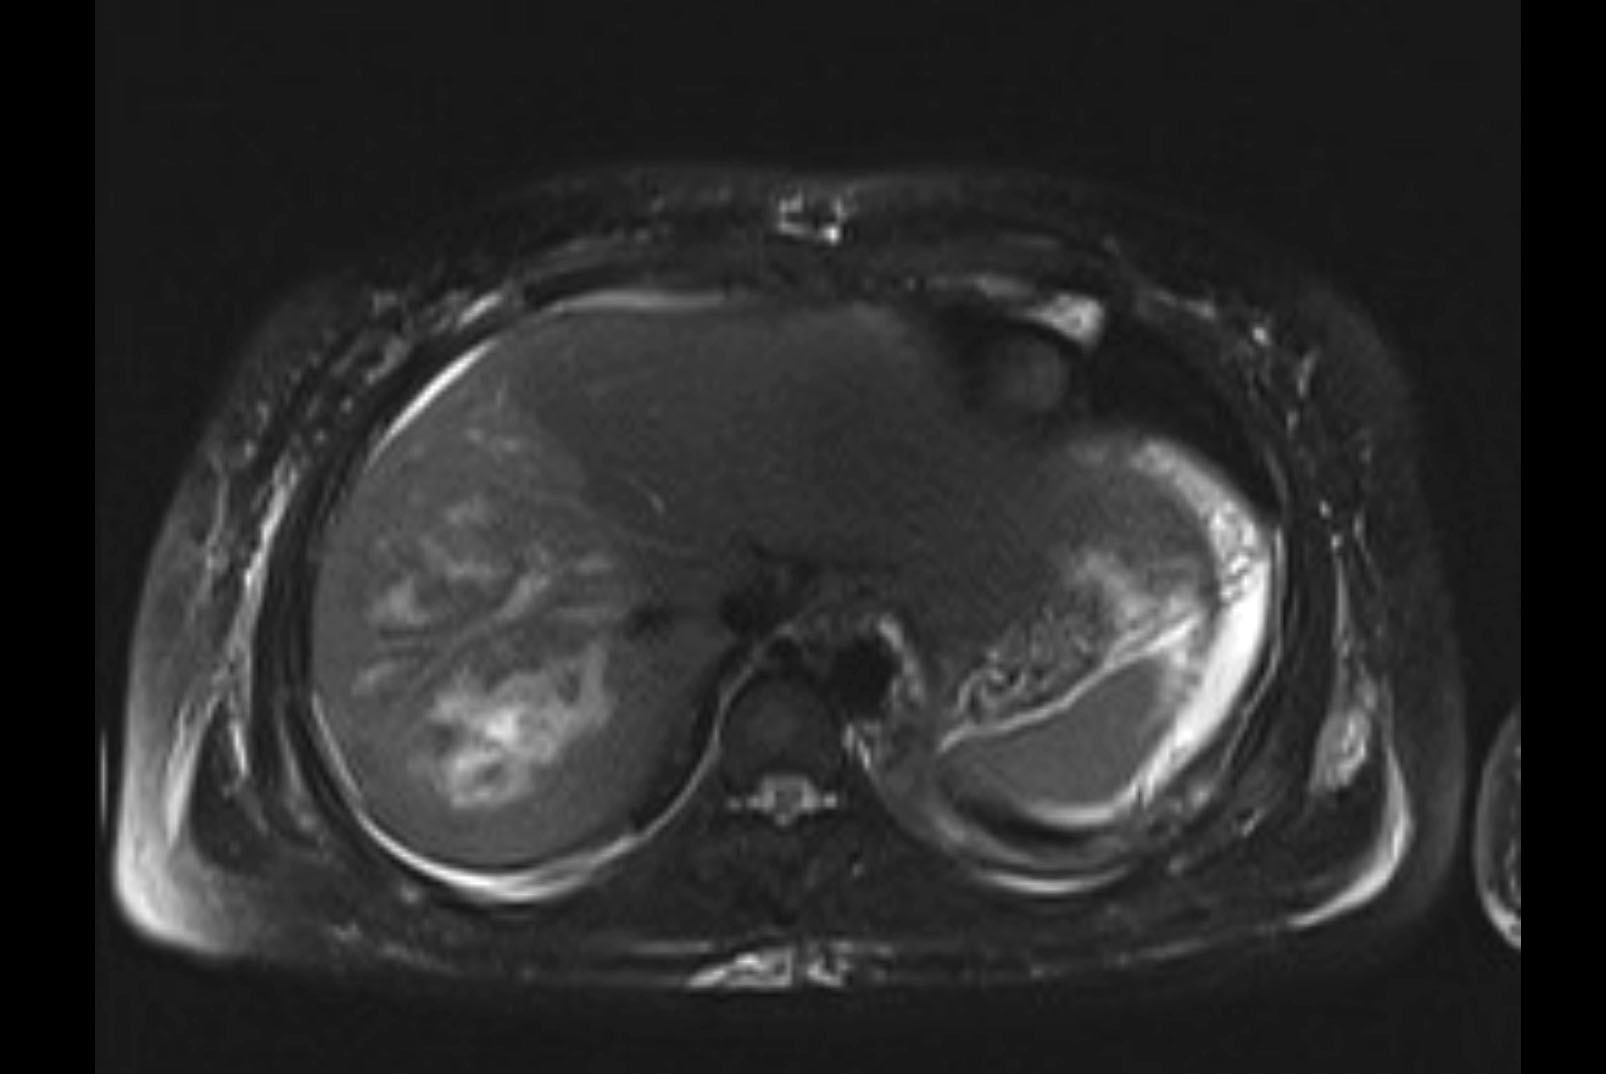

MRI T2

Imaging analysis

Based on initial findings, which issue(s) would you be most concerned about?